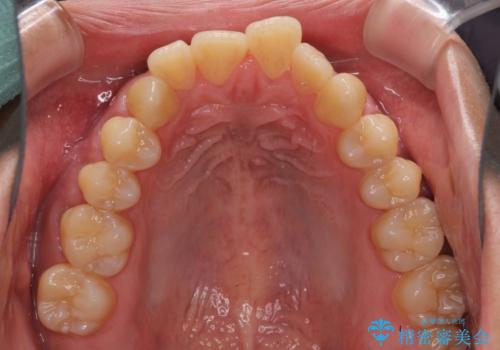

- 上下前歯の隙間と口元の出っ張った感じを気にして来院された患者様です。

上下の隙間は舌突出癖によるもので、またその癖により前歯が前方に出ている状態でした。

口元の出っ張りを改善するため、上下左右第一小臼歯4本を抜去し、ワイヤー装置にて矯正治療を行うこととしました。